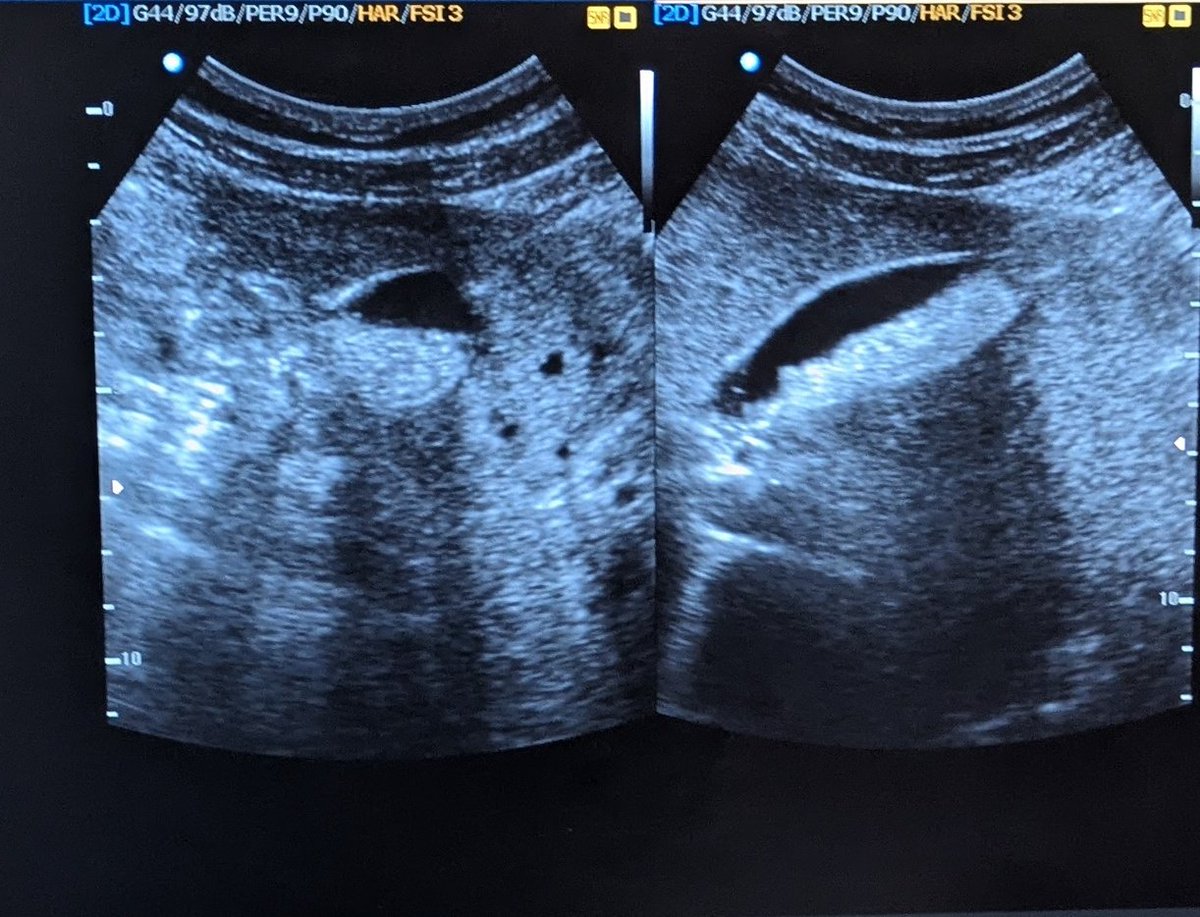

@popoolaadaniel First image: reversed end diastolic flow: ?iugr second: absent end diastolic flow: ? Placental insufficiency or issues Third image: normal sharp systolic forward flow followed by normal end diastolic flow just inverted